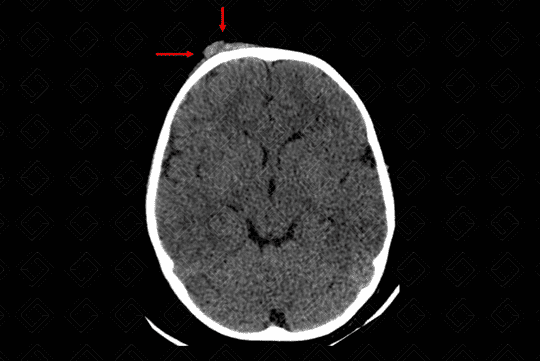

Texto alternativo para a imagem Figura 2. Créditos: Dra Elazir Mota - Rio de Janeiro/RJ

Descrição da lesão: Traumatismo cranioencefálico na criança. Tomografia computadorizada do crânio com reconstrução tridimensional (3D): presença de volumoso hematoma subgaleal na região frontal direita (figura 1, setas vermelhas). Na reconstrução tridimensional, nota-se o traço de fratura na mesma topografia com extensão ao teto da órbita deste lado, sem desalinhamento ósseo significativo (figura 2 e 3).